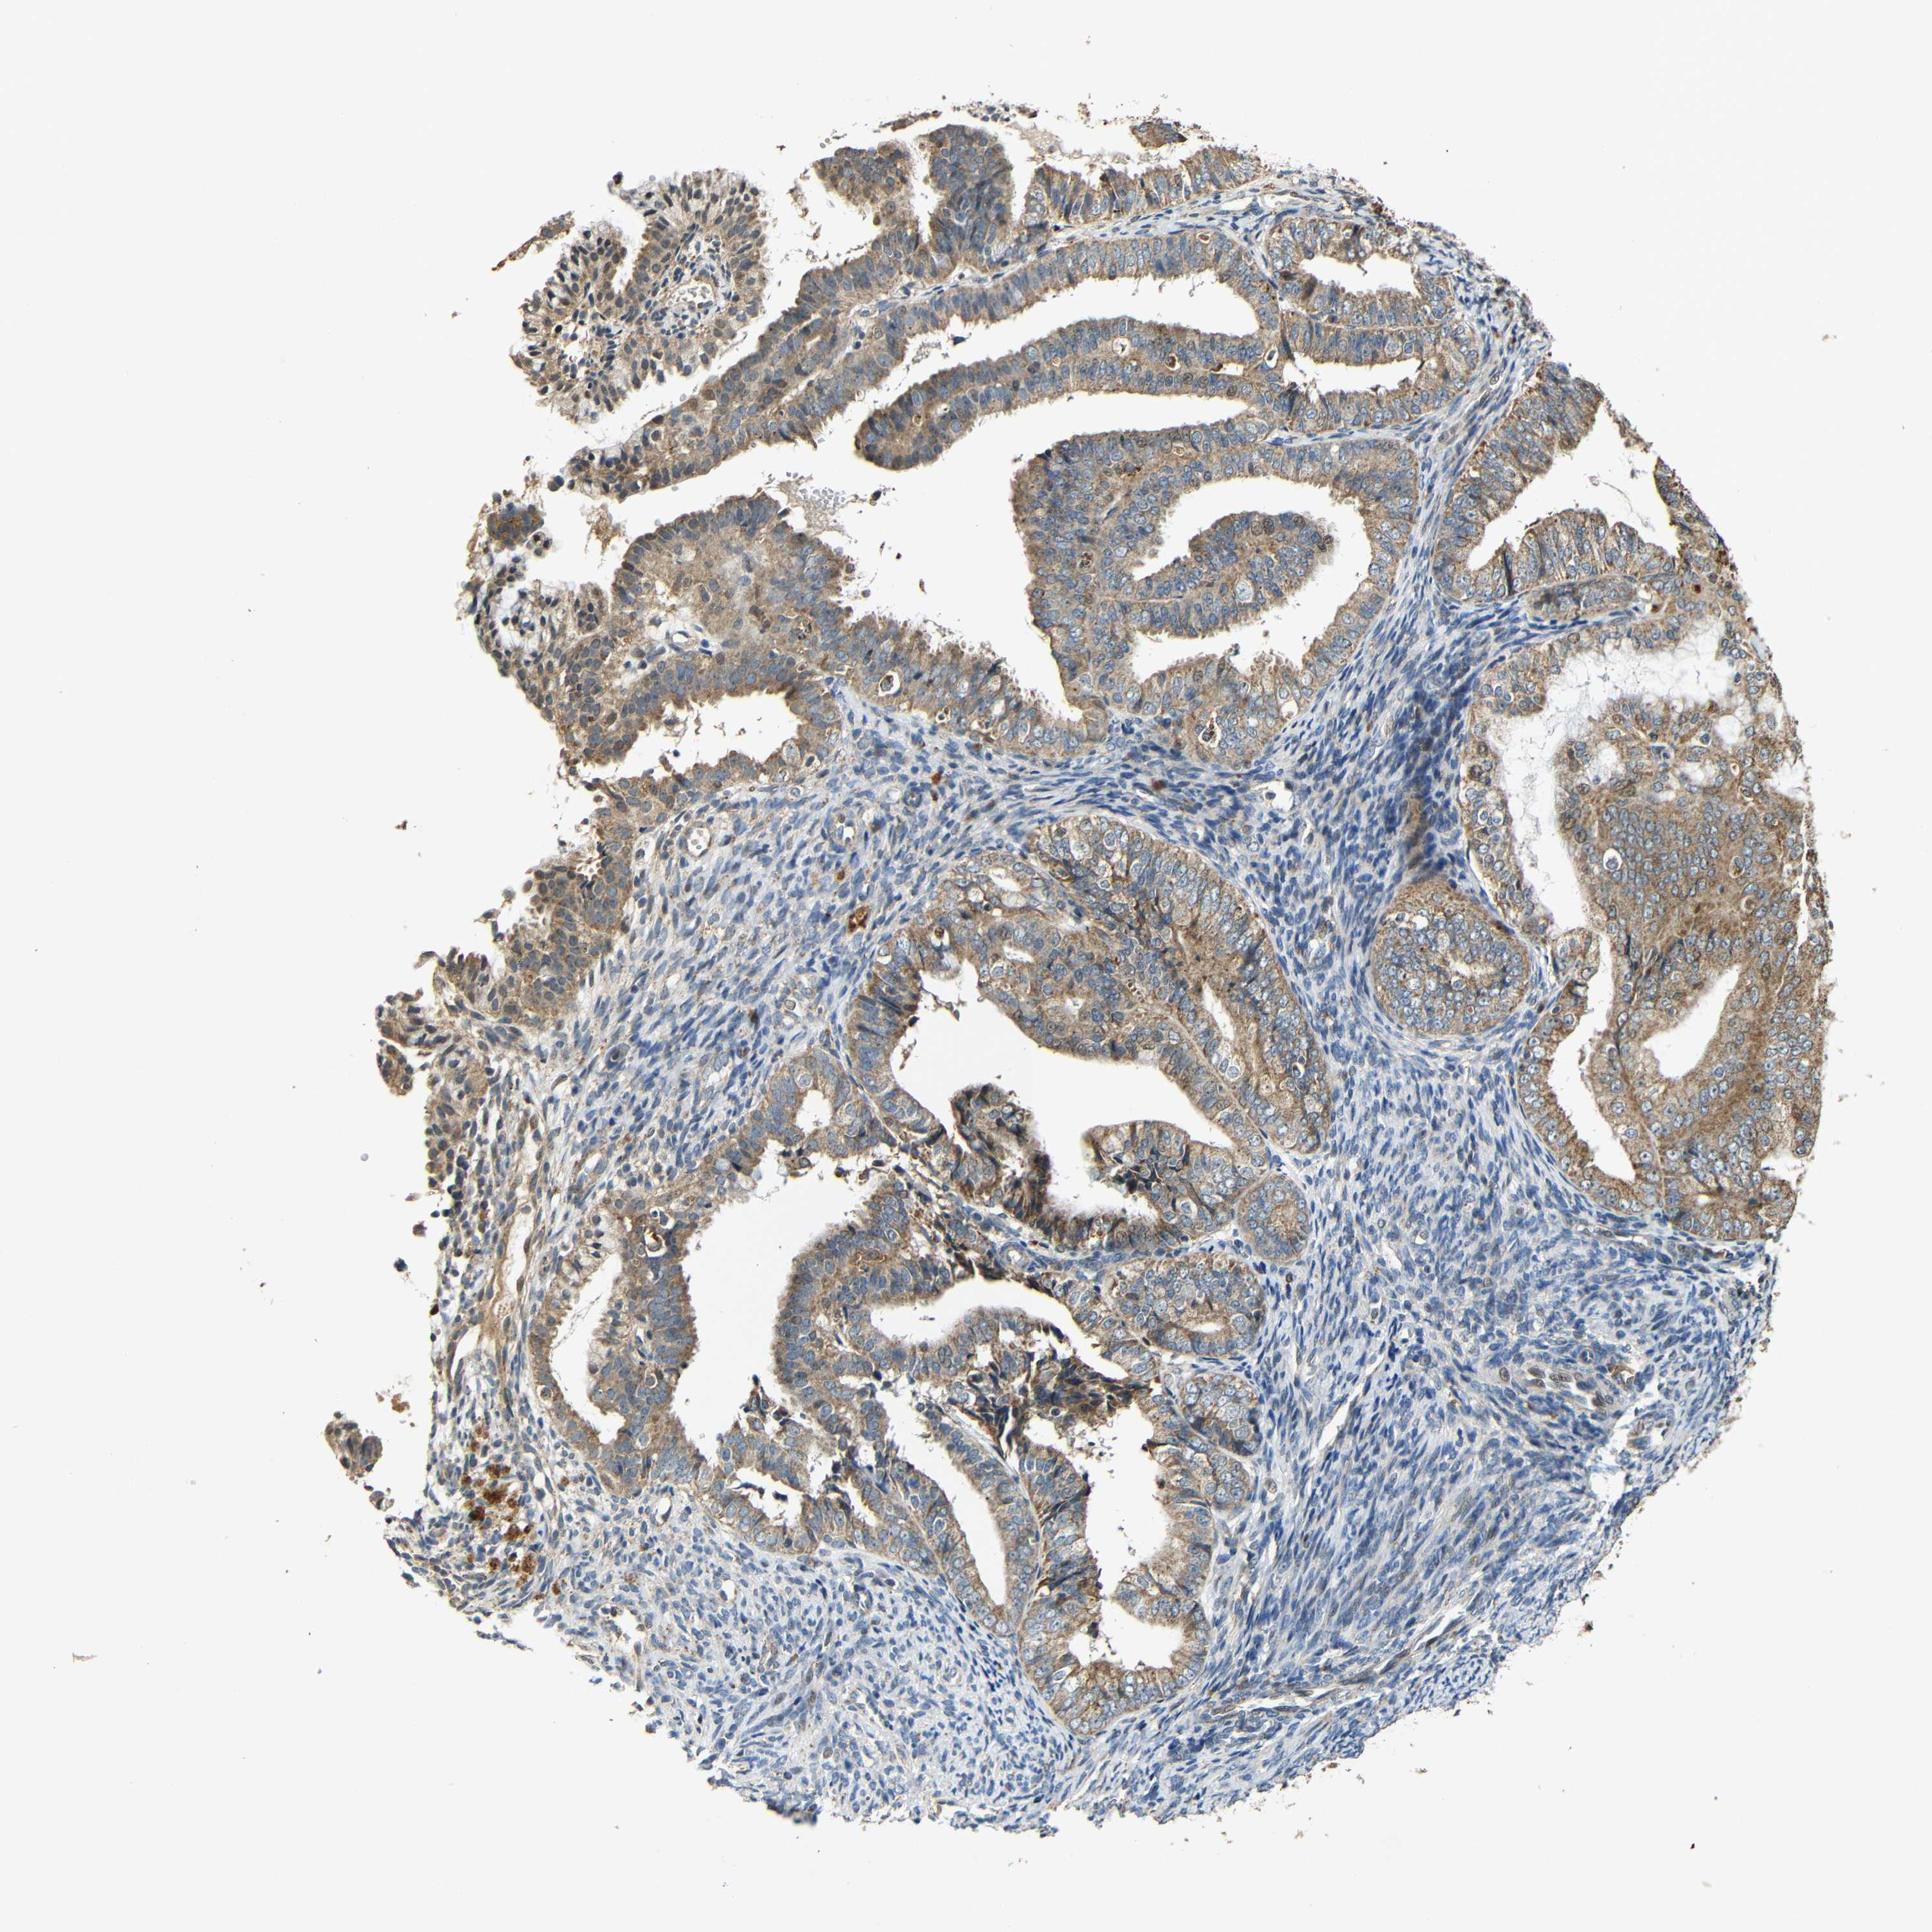

ENDOMETRIAL CANCER - Protein expressioni

A mouse-over function shows sample information and annotation data. Click on an image to view it in a full screen mode. Samples can be filtered based on level of antibody staining by selecting one or several of the following categories: high, medium, low and not detected. The assay and annotation is described here.

Note that samples used for immunohistochemistry by the Human Protein Atlas do not correspond to samples in the TCGA dataset.

Antibody stainingi

Antibody staining in the annotated cell types in the current human tissue is reported as not detected, low, medium, or high, based on conventional immunohistochemistry profiling in selected tissues. This score is based on the combination of the staining intensity and fraction of stained cells.

Each image is clickable and will lead to virtual microscopy that enables deeper exploration of all samples and also displays staining intensity scores, fraction scores and subcellular localization as well as patient and tissue information for each sample.

Antibody HPA011800

Staining

High

Medium

Low

Not detected

Intensity

Strong

Moderate

Weak

Negative

Quantity

>75%

75%-25%

<25%

None

Location

Nuclear

Cytoplasmic/membranous

Cytoplasmic/membranous,nuclear

Adenocarcinoma, NOS